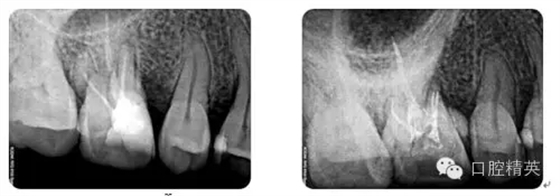

病例2:各型MB2根管

病例3:C型根管